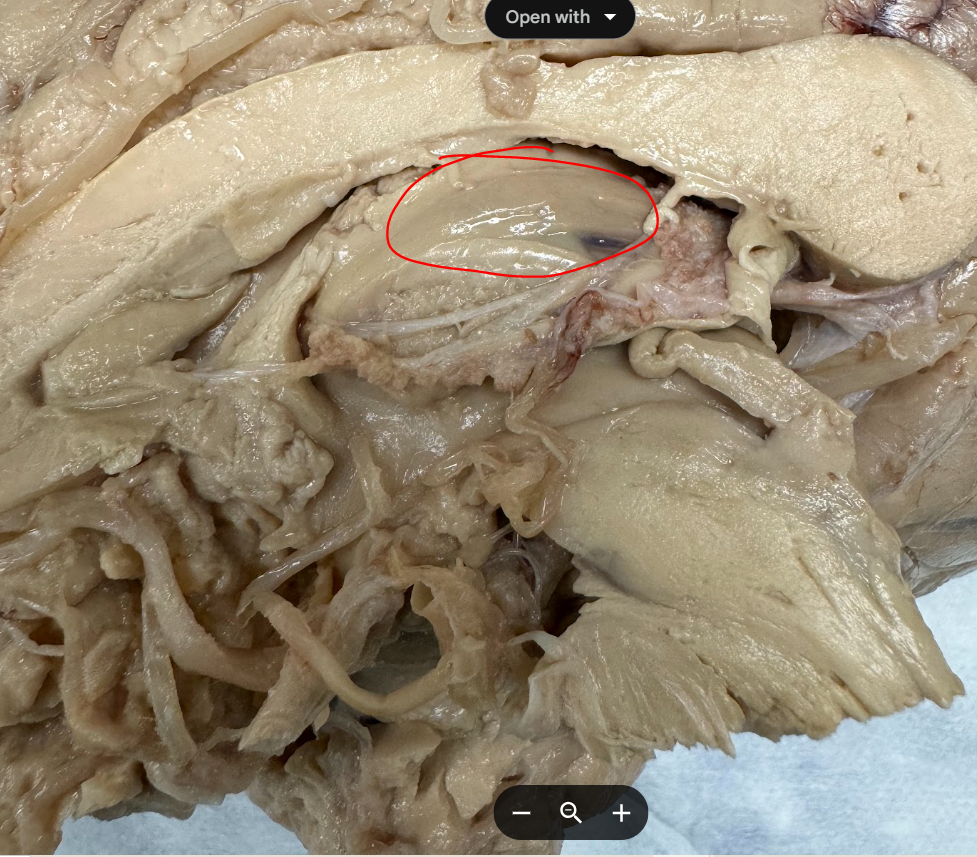

3rd ventrical

choroid plexus

Corpus Callosum